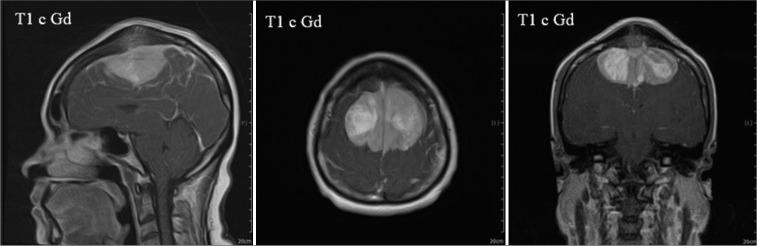

A 47-year-old woman presented with psychomotor retardation and subtle weakness, particularly on the left side. A palpable mass was identified at the head vertex. Magnetic resonance imaging revealed bilateral parasagittal meningiomas with bone and sinus invasion of the SMA. A craniotomy was performed to remove the intracapsular tumor. Two days after the operation, the patient developed gradual deterioration in her motor function until it became a lock-in-like syndrome. Then, 1.5 months after treatment in the hospital and rehabilitation unit, she gradually improved her motor, cognitive, and psychomotor skills. Total recovery was achieved after 1 year.

一名47岁女性表现为精神运动迟缓及轻微无力,尤其是左侧。在头顶可触及肿块。磁共振成像显示双侧矢状窦旁脑膜瘤伴SMA骨质及窦侵犯。行开颅手术切除囊内肿瘤。术后两天,患者运动功能逐渐恶化,直至出现类似闭锁综合征。然后,在医院和康复科治疗1.5个月后,她的运动、认知和精神运动技能逐渐改善。1年后实现完全康复。